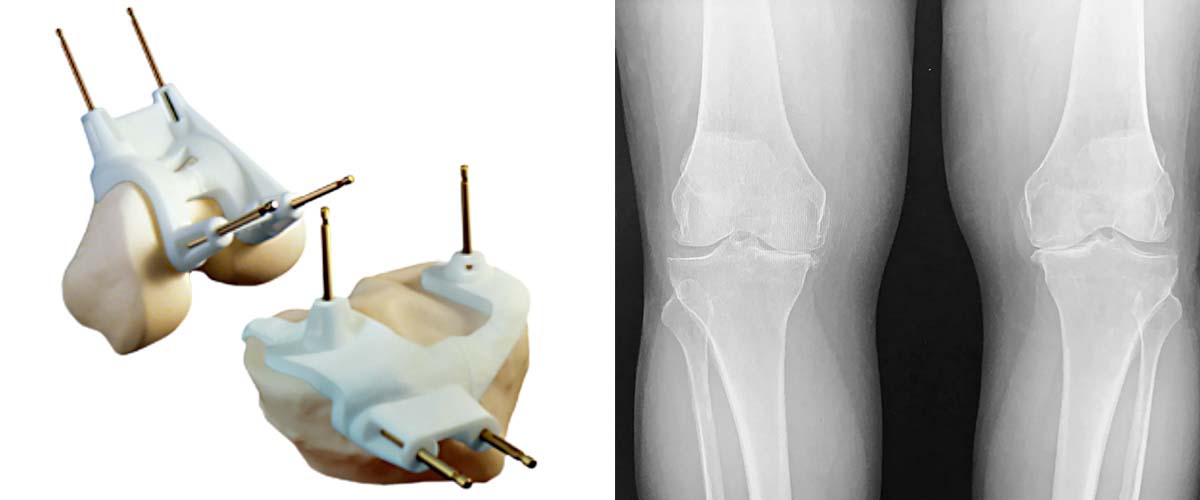

Προτείνεται η εξατομικευμένη αρθροπλαστική γόνατος PSI (Patient Specific Instrumentation) η οποία διαφοροποιείται από την κλασική τεχνική της αρθροπλαστικής γόνατος, καθώς η πρόθεση που τοποθετείται στις φθαρμένες αρθρικές επιφάνειες κατασκευάζεται πλήρως στις ανάγκες του ασθενούς λαμβάνοντας υπ’ όψιν τις ειδικές κλίσεις και στροφές που έχει όλο το κάτω άκρο. Με αυτό τον τρόπο προσφέρεται εξαιρετική ακρίβεια κατά την εμφύτευση της πρόθεσης μέσω ειδικών εργαλείων που λειτουργούν ως οδηγοί.

Για να επιτευχθεί η ολική αρθροπλαστική γόνατος PSI πραγματοποιείται προεγχειρητικός έλεγχος με διενέργεια αξονικής τομογραφίας τριών σημείων: ισχίου, γόνατος και ποδοκνημικής. Έπειτα οι εξετάσεις αποστέλλονται σε ειδικό κέντρο στο εξωτερικό, στο οποίο γίνεται η κατασκευή των οδηγών τοποθέτησης και του εμφυτεύματος σε συνεργασία πάντα με τον θεράποντα ιατρό. Το συγκεκριμένο εμφύτευμα μπορεί να εφαρμοστεί μόνο στον συγκεκριμένο ασθενή.